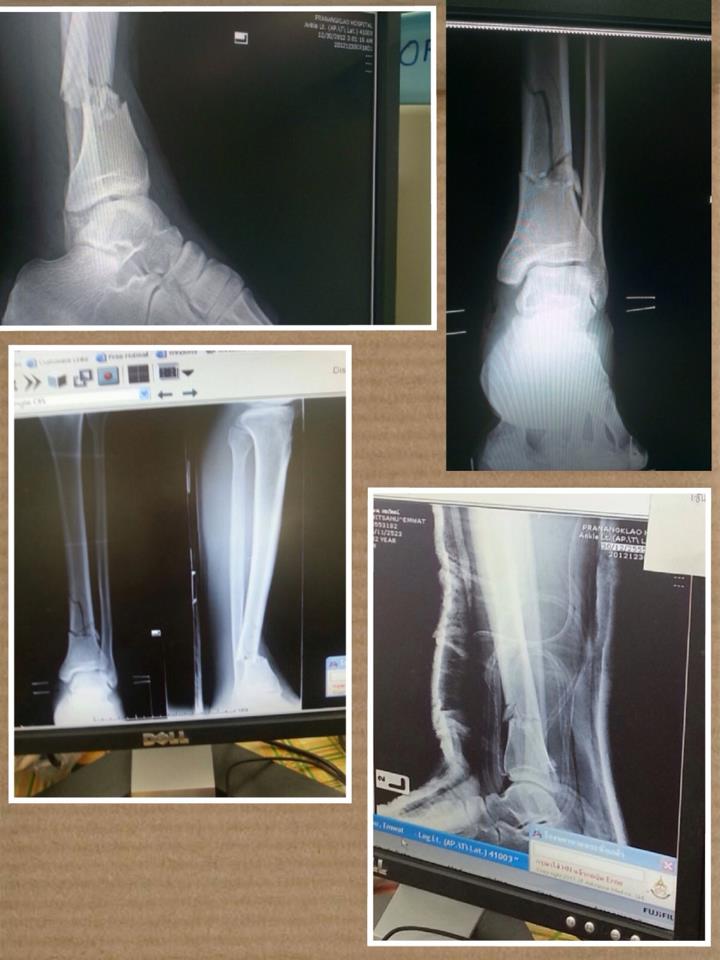

ตอนนนี้เพื่อนผมรักษาตัวอยู่ที่ รพ.พระนั่งเกล้าได้ 2 อาทิตยืกว่าแล้ว ผ่าตัดไป 2 ครั้ง และยังไม่รู้ว่าจะหายเมื่อไหร่ ค่าใช้จ่ายในการรักษา คาดว่าประมาณ แสนบาท

รูป X-Ray กระดูกแตก